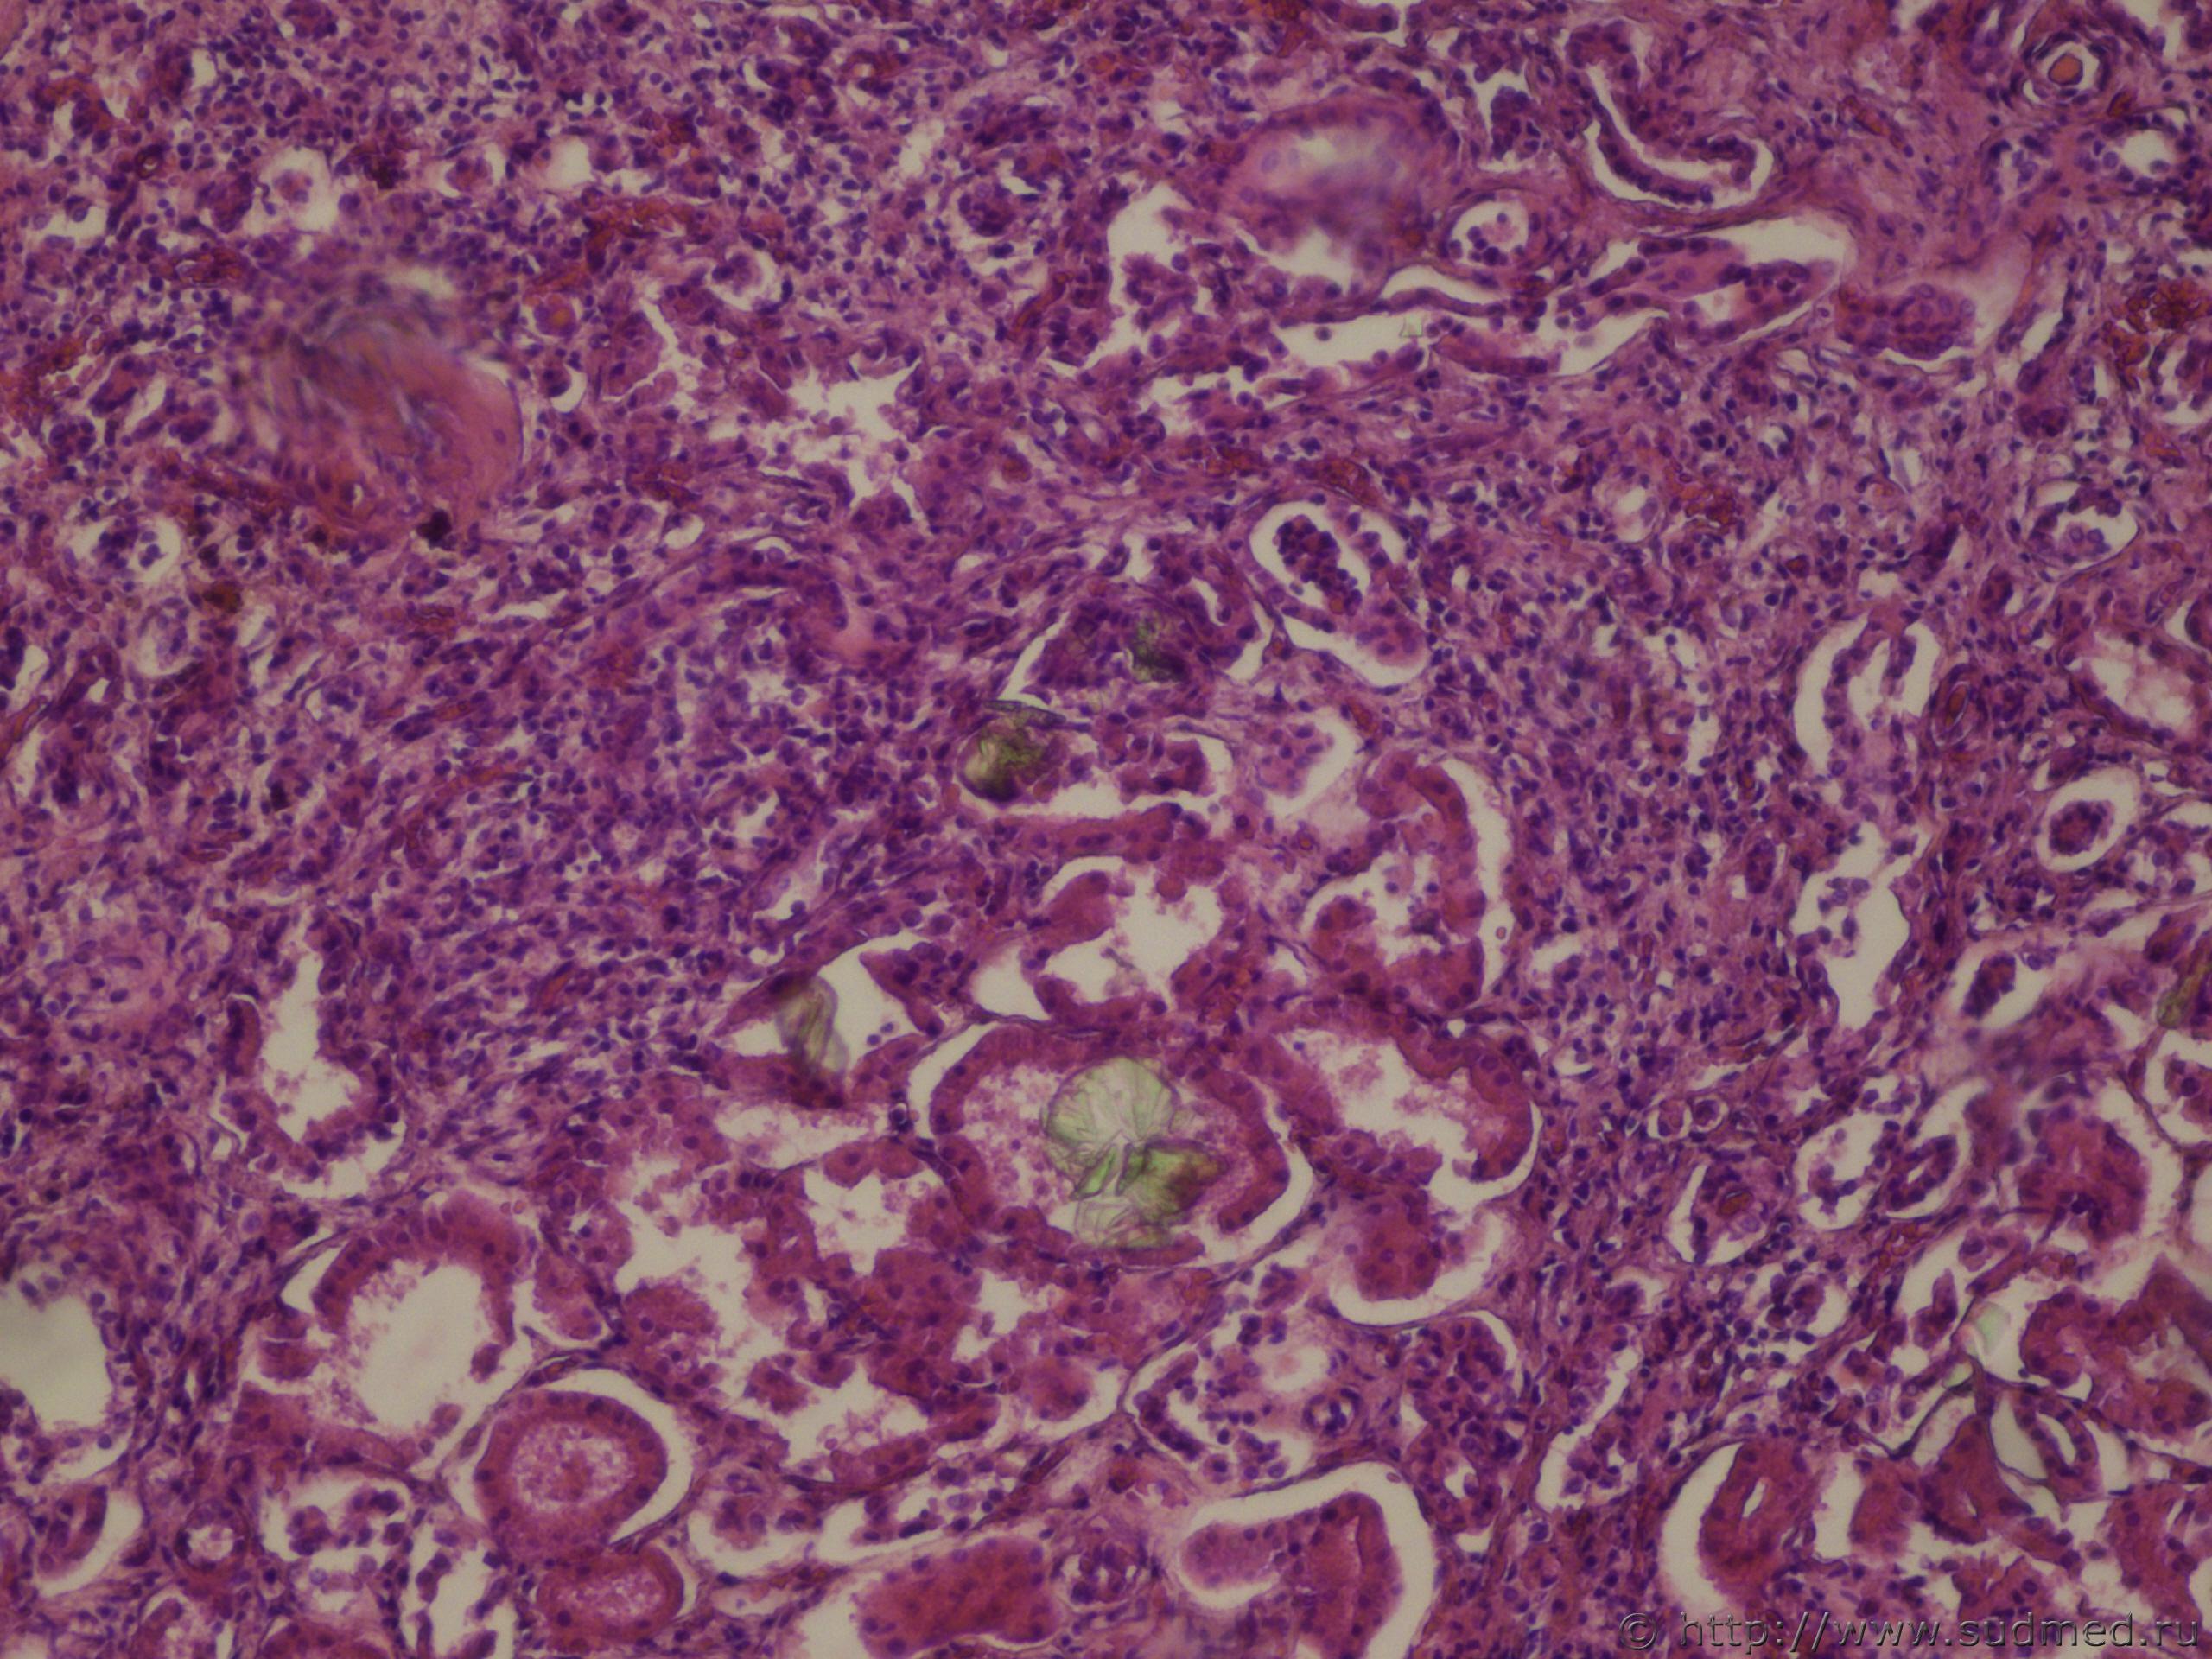

Грибковый сепсис (криптококкоз)

Фото 1. Почка

Фото 2,3. Головной мозг

Фото 4,5,6. Головной мозг (иммерсия)

Окраска по Боголепову